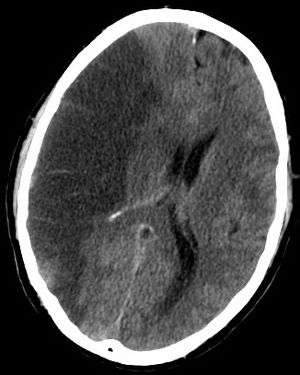

CT scan slice of the brain showing a right-hemispheric cerebral infarct (left side of image). | |